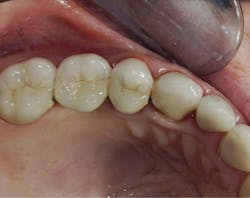

Figure 3: The second molar had about one-half of the coronal tooth structure removed and required a resin-based composite buildup. The first premolar had only a Class I defect and received a filler of bonded compomer (Dyract). The canine received a fiber-reinforced post, two pure titanium pins on the lingual (Filpins from Filhol Dental), and a resin-based composite coronal buildup.

Figure 4: These final restorations have now served for 15 years.